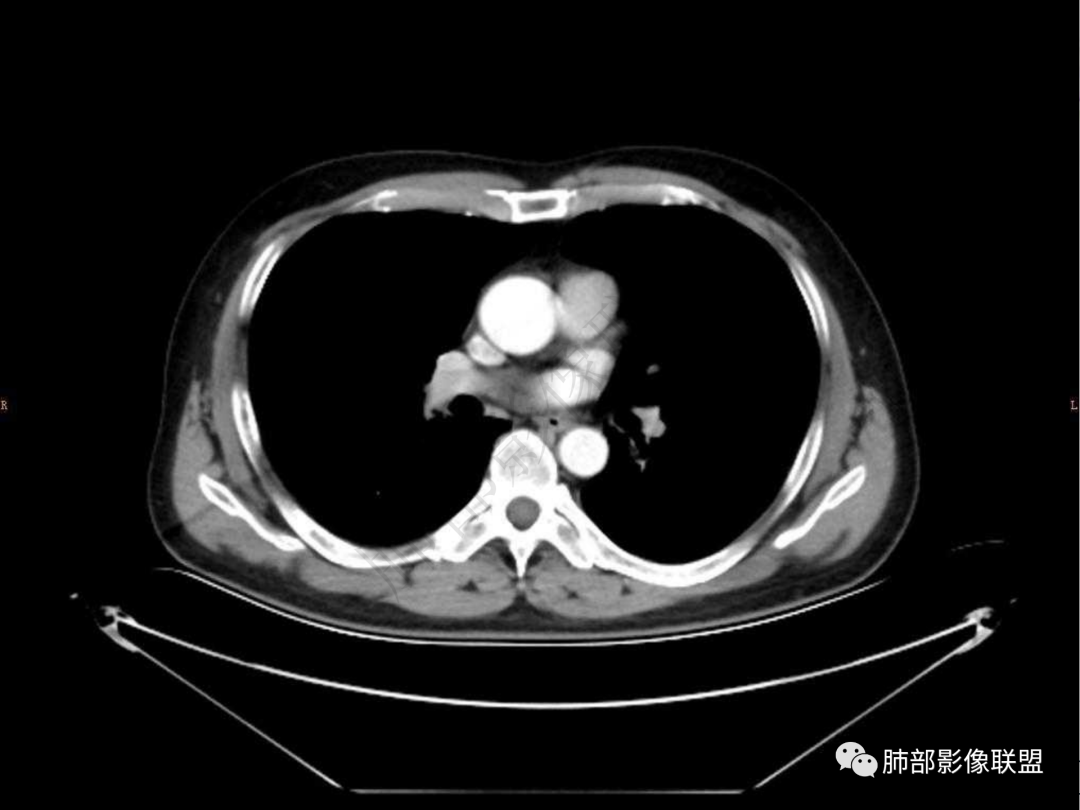

4.实性部分不均匀环形强化并显示一小范围低密度坏死区或空洞。较之肺窗,整体纵隔窗范围较小,提示病灶并不十分密实。抑或为不同时段图像。

5.双肺门及纵隔未见增大淋巴结。未见胸腔积液。